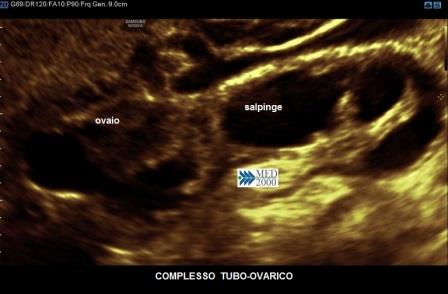

E' possibile, ma non sempre, osservare anche un versamento pelvico. Quando il processo infiammatorio si estende anche all'ovaio si ha il cosiddetto complesso tubo-ovarico caratterizzato dalla presenza di una tumefazione dovuta alla salpinge distesa da pus ed aderente all'ovaio in una unica massa nella quale sono ben distinguibili sia la tuba che l'ovaio.